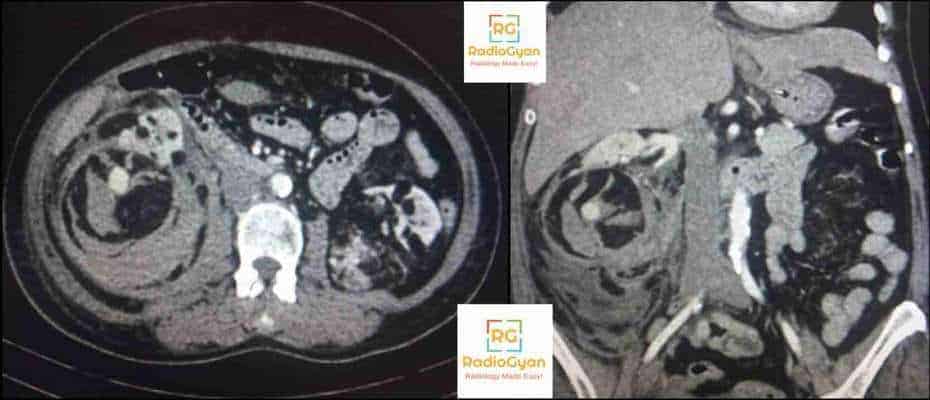

Genitourinary Radiology Cases – Spotter Set 9 Read More ยปGenitourinary Radiology Cases – Spotter Set 9